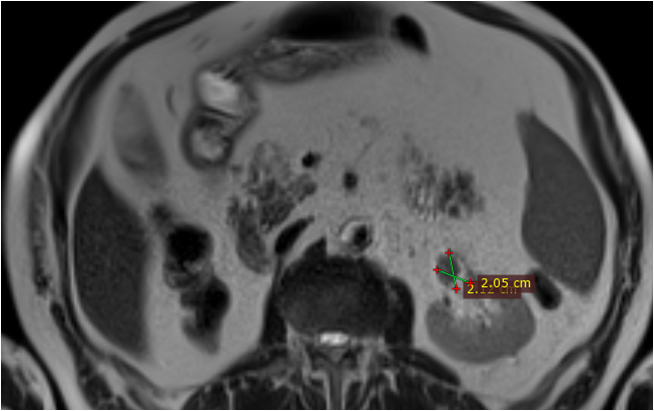

Під час проведення профілактичного УЗД у нього було виявлено пухлину правої нирки.

Основний: T-r (2 пухлини) правої нирки сT2 N0 M0 Gх ст ІI, кл.гр 2.

Супутній: Кісти нирок.